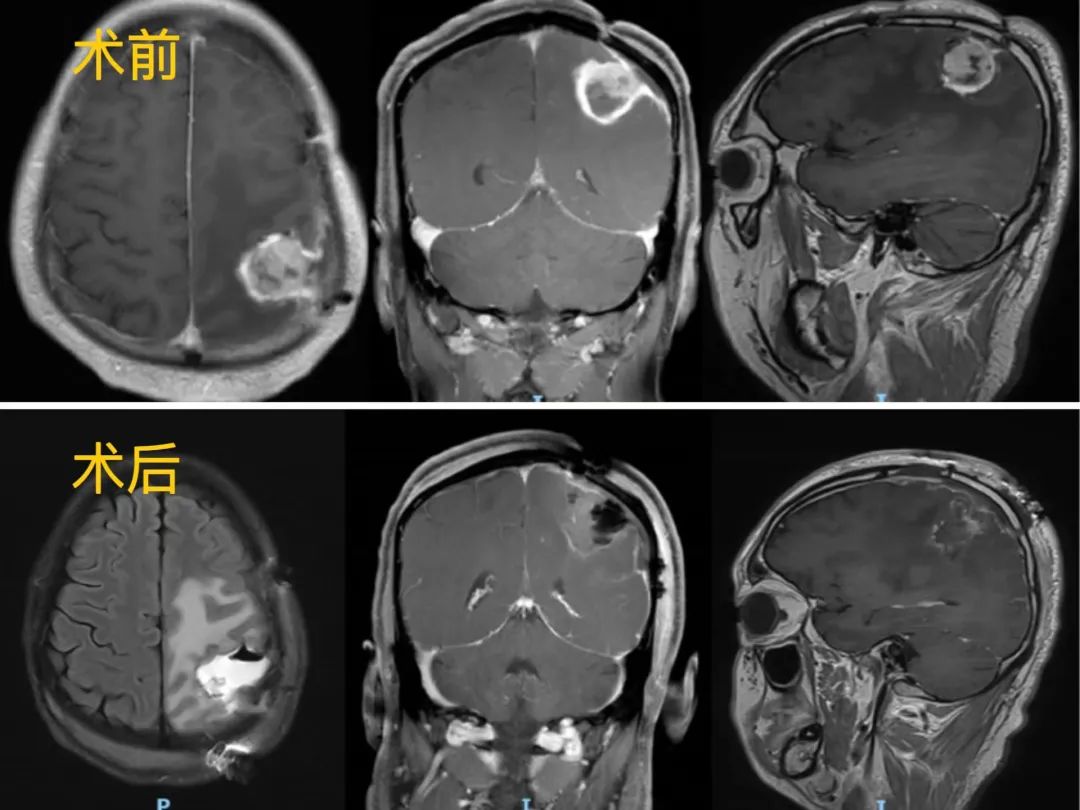

(术前:磁共振提示肿瘤复发于原术区后内方,累及中央后回、顶上小叶和顶下小叶。术后:磁共振提示肿瘤完全切除。)

患者石先生(化名)今年37岁,此前曾做过左侧顶叶肿瘤切除术,术后18个月因癫痫发作入院。检查发现身体右侧上肢肌力从正常的5级下降到4级。头颅MRI检查发现有一颗5厘米的肿瘤,更加糟糕的是,肿瘤侵犯中央后回及顶上小叶,靠近中央前回、缘上回等重要功能区,这些区域损伤可出现偏瘫、偏身感觉障碍、失写、失算、失用等症状。

在历时7个小时的手术中,医务人员通过实时监测、查看电生理的异常变化避开神经功能区,在保证了重要的功能结构不被破坏的前提下,完整地切除了肿瘤。手术顺利结束,术后经脱水、抗炎、对症处理及精心护理治疗,患者恢复良好,神经功能得到明显改善。